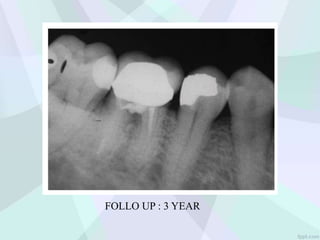

FOLLO UP : 3 YEAR

Repair of FurcalIatrogenic Perforation with Mineral Trioxide Aggregate

FOLLO UP :3 YEAR